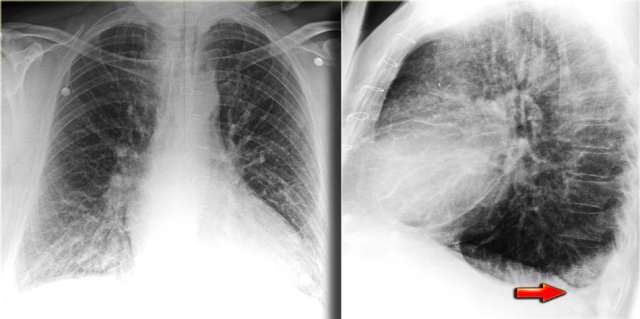

On the left images of a patient who has bilateral pleural effusions.

Notice that it is more evident on the lateral view.

Pleural effusion is not always visible as a meniscus in the costophrenic angle.

A subpulmonic effusion may follow the contour of the diaphragm making it tricky to discern.

In these cases, the only way to detect pleural effusion, is when you notice that there is an increased distance between the stomach bubble and the lung.

The stomach is normally located directly under the diaphragm, so, on an erect PA radiograph, the stomach bubble should always appear in close proximity to the diaphragm and the lung.

On the left images of a patient with signs of CHF.

At first glance you might get the impression that there is a high position of the diaphragm.

However when you notice the increased distance of the stomach air bubble to the lung base, you realize that there is a large amount of pleural fluid on both sides (arrow).